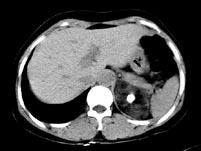

问题 男性,28岁,左腰背酸胀5个月,CT检查如图所示,应诊断为 ( )

选项 A、左肾上腺腺瘤 B、左肾上腺转移瘤 C、左肾上腺错构瘤 D、左肾上腺嗜铬细胞瘤 E、左肾上腺髓样脂肪瘤

答案 C